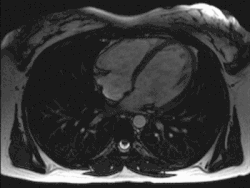

![]() Un trasplante de corazón pone a todo el mundo ante dilemas éticos. | |||||

La IRM muestra un quiste en la vesícula biliar. Descartan la posibilidad de que sea adenoma o hemangioma cavernoso. A House se le ocurre que podría ser una amebiasis y ordena administrar paromomicina y cloroquina en dosis 20 veces mayores que las recomendadas, debido a que la persona se encuentra muerta y por lo tanto los efectos secundarios no pueden afectarla.